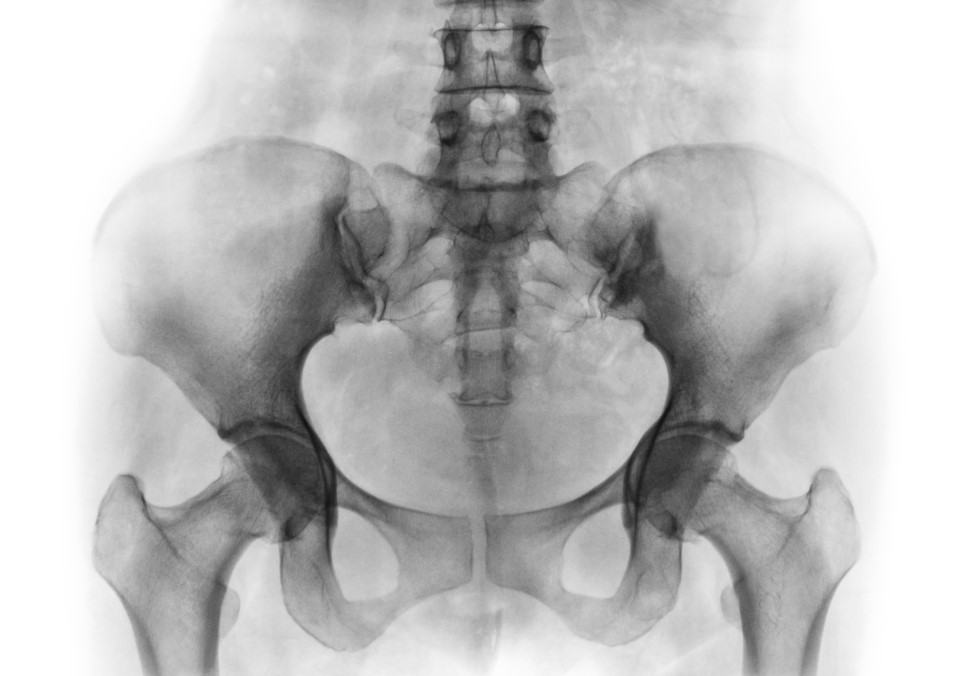

가볍게 걷기만 해도 고관절이나 허리, 엉덩이 주변에 통증이 느껴진다면?

허리디스크 등 척추질환이 없음에도 불구하고, 고관절이나 허리 통증이 반복된다면 골반 틀어짐을 의심해보아야 합니다.

골반은 우리 신체의 가운데에서 척추를 지지하면서 체중을 다리로 분산하는 역할을 하고 있습니다. 즉, 몸의 균형을 잡아주는 기관으로 골반이 틀어지면 양쪽 다리 길이에 차이가 생기고, O자 다리, X자 다리 등 하체 변형과 각종 척추 질환의 원인이 되므로 교정하는 것이 중요합니다.